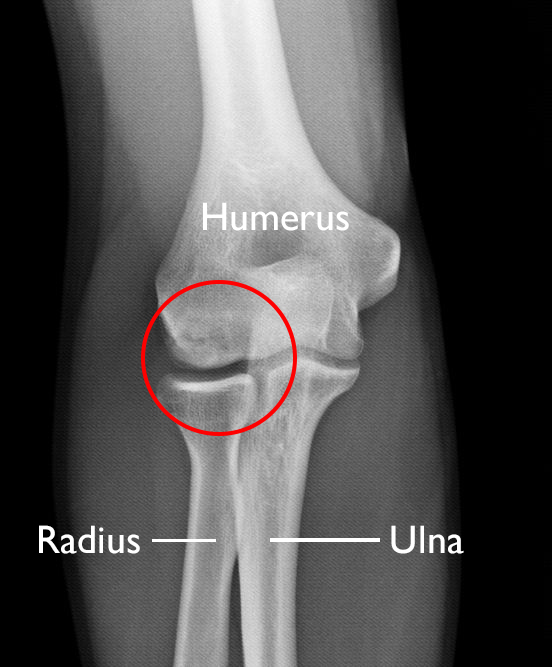

OCD lesion in elbow

This X-ray shows an OCD lesion (circled) in the humerus (upper arm bone) of a teenager.

Image courtesy of Stuart J. Fischer, MD, FAAOS